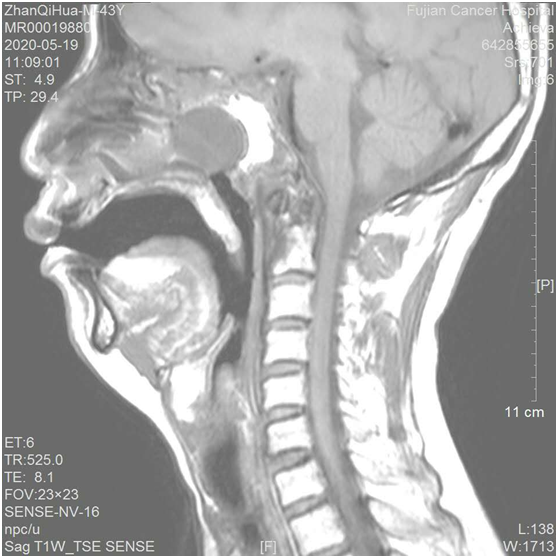

患者9年前因“鼻咽癌”在我院治疗,1个月前到我院复查诊断显示鼻咽深大溃疡形成伴颅底、C1右侧块骨质破坏,为防止感染合并复发可能,头颈外科收治入院进行治疗。入院后在科主任刘辉教授的周密安排下,制定了精密的手术方案,经过充分术前准备,在全麻下进行了"鼻内镜下颅底肿瘤切除术+鼻窦开放术+右颞肌瓣修复术+气管切开术"。手术过程中发现鼻咽部巨大溃疡、斜坡骨质坏死、左侧溃疡达左破裂孔、溃疡表面被覆脓苔等症状,常规鼻中隔粘膜瓣已无法提供有效的修复与保护,决定进行右颞肌瓣修复颅底巨大缺损手术。手术过程顺利,术后3天复查MR示溃疡已切除,颞肌瓣成活良好。术后10天病人安全康复出院。